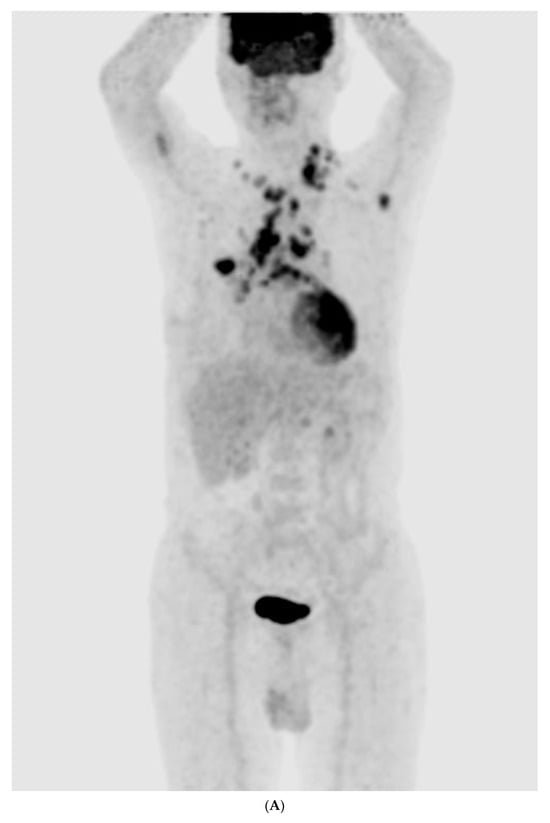

The chest radiography showed a massive right-sided pleural effusion (Figure 1A). Percutaneous catheter drainage was performed for the right-sided pleural effusion. The chest computed tomography showed a 3.3 cm × 3.0 cm mass in the right upper lobe (Figure 1B). The positron emission tomography/computed tomography revealed metastases in the left-sided supraclavicular lymph nodes, multiple bilateral mediastinal lymph nodes, and left scapula (Figure 2). The magnetic resonance imaging of the brain revealed multiple tiny cerebral and right cerebellar metastases (Figure 3). A percutaneous needle biopsy confirmed the diagnosis of lung adenocarcinoma (pT2aN3M1c, stage IVB); the analysis of the right-sided pleural effusion revealed metastatic adenocarcinoma. The genetic analysis revealed an exon 19 deletion in the EGFR gene. The laboratory tests, including the blood cell counts and chemistry, were within the normal ranges prior to treatment initiation. The patient was administered the EGFR-TKI afatinib (40 mg/day) as a first-line chemotherapy.

Figure 2.

(A–E) Positron emission tomography/computed tomography revealed metastases to multiple lymph nodes, includingleft supraclavicular lymph node, bilateral mediastinal areas, and left scapula.